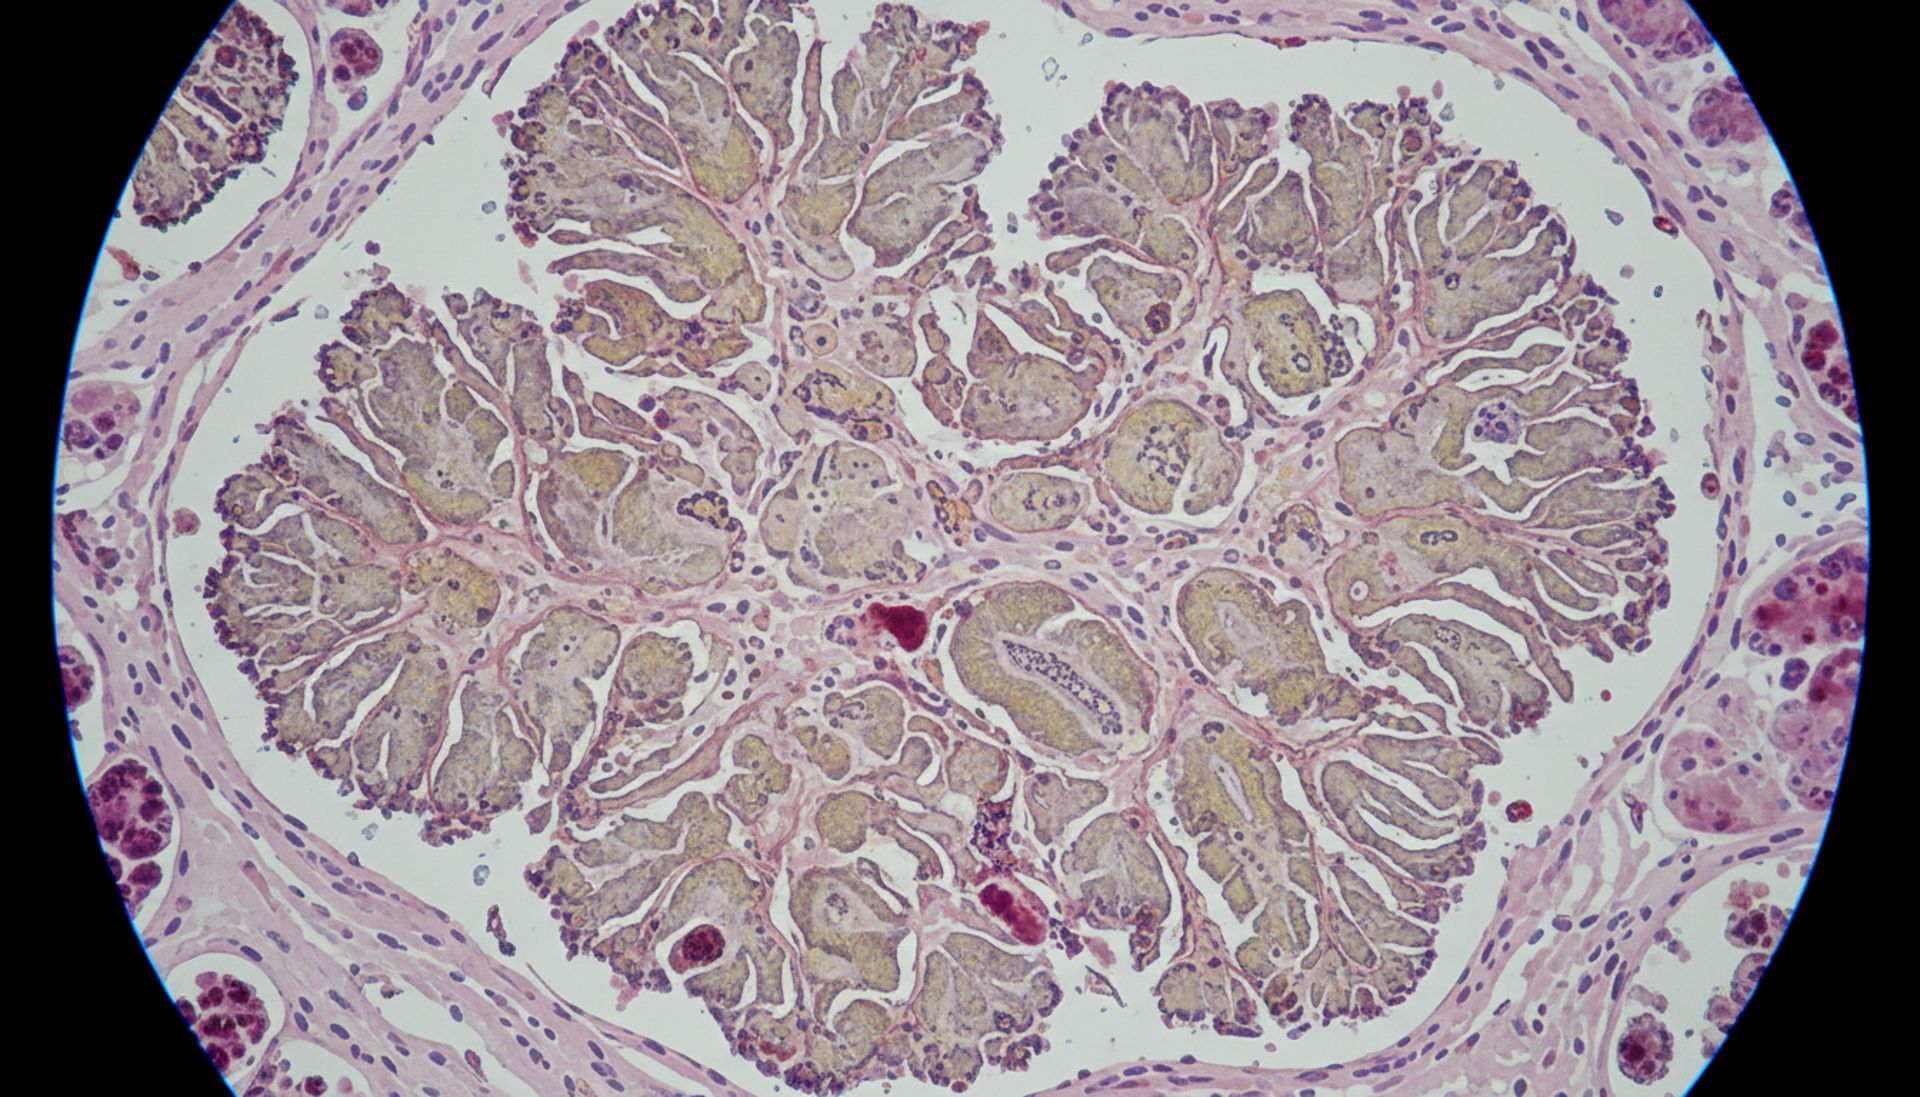

- Biopsja endometrium – pobranie materiału do badania histopatologicznego.

- Histeroskopia – wizualna ocena i precyzyjne pobranie wycinków.